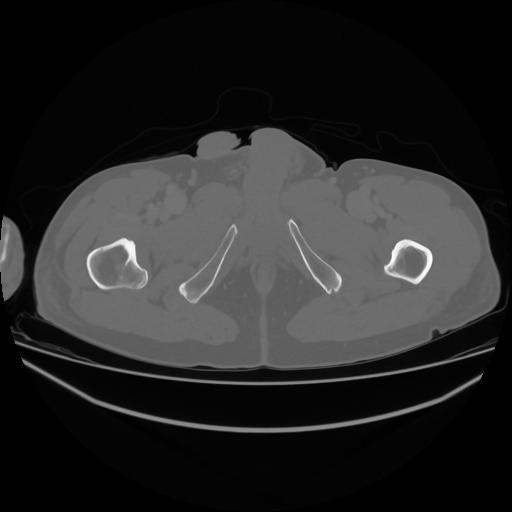

5 CUERPO,CE,Vol,1.0,CUERPO,,